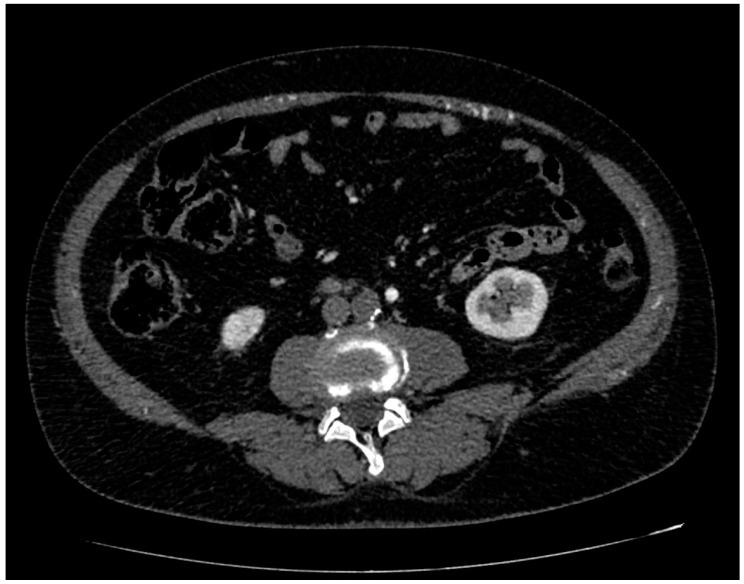

Primary aortic occlusion (PAO) is defined as acute occlusion in the absence of aortic atherosclerosis or aneurysm. PAO is a rare disease with acute onset and can determine massive parenchymal ischemia and distal arterial embolization. The aim of our study was to focus on the assessment of clinical characteristic, CT signs, medical and surgical treatment, complication rates and the overall survival of PAO.

A total of 11 patients (8 males/3 females; male/female ratio, 2.66:1, age range 49 to 79 years-old, mean age 65.27 y/o) with acute onset of lower limb impotence or ischemia were diagnosed with PAO. The etiology was thrombosis in all patients. The aortic occlusion was always located in the abdominal aorta and extended bilaterally through the common iliac arteries. The upper limit of the thrombosis was detected in the aortic subrenal tract in 81.8% of the cases, and in the infrarenal tract in 18.2%. A total of 81.8% of the patients were referred to the ER for symptoms related to lower limb: bilateral acute pain, hypothermia and sudden onset of functional impotence. Two patients (18.2%) died before undergoing surgery for multi-organ failure determined by the severe acute ischemia. The other patients (81.8%) underwent surgical treatment that included aortoiliac embolectomy (54.5%), aortoiliac embolectomy + aorto-femoral bypass (18.2%) and aortoiliac embolectomy and right lower limb amputation (9.1%). The overall mortality was 36.4% while the estimated survival at 1 year was 63.6%.

PAO is a rare entity with high morbidity and mortality rates if not recognized and treated promptly. Acute onset of lower limb impotence is the most common clinical presentation of PAO. Aortic CT angiography is the first-choice imaging technique for the early diagnosis of this disease and for the surgical treatment, planning and assessment of any complications. Combined with surgical treatment, anticoagulation is considered the first-line medical therapy at the time of diagnosis, during surgical treatment and after at discharge.